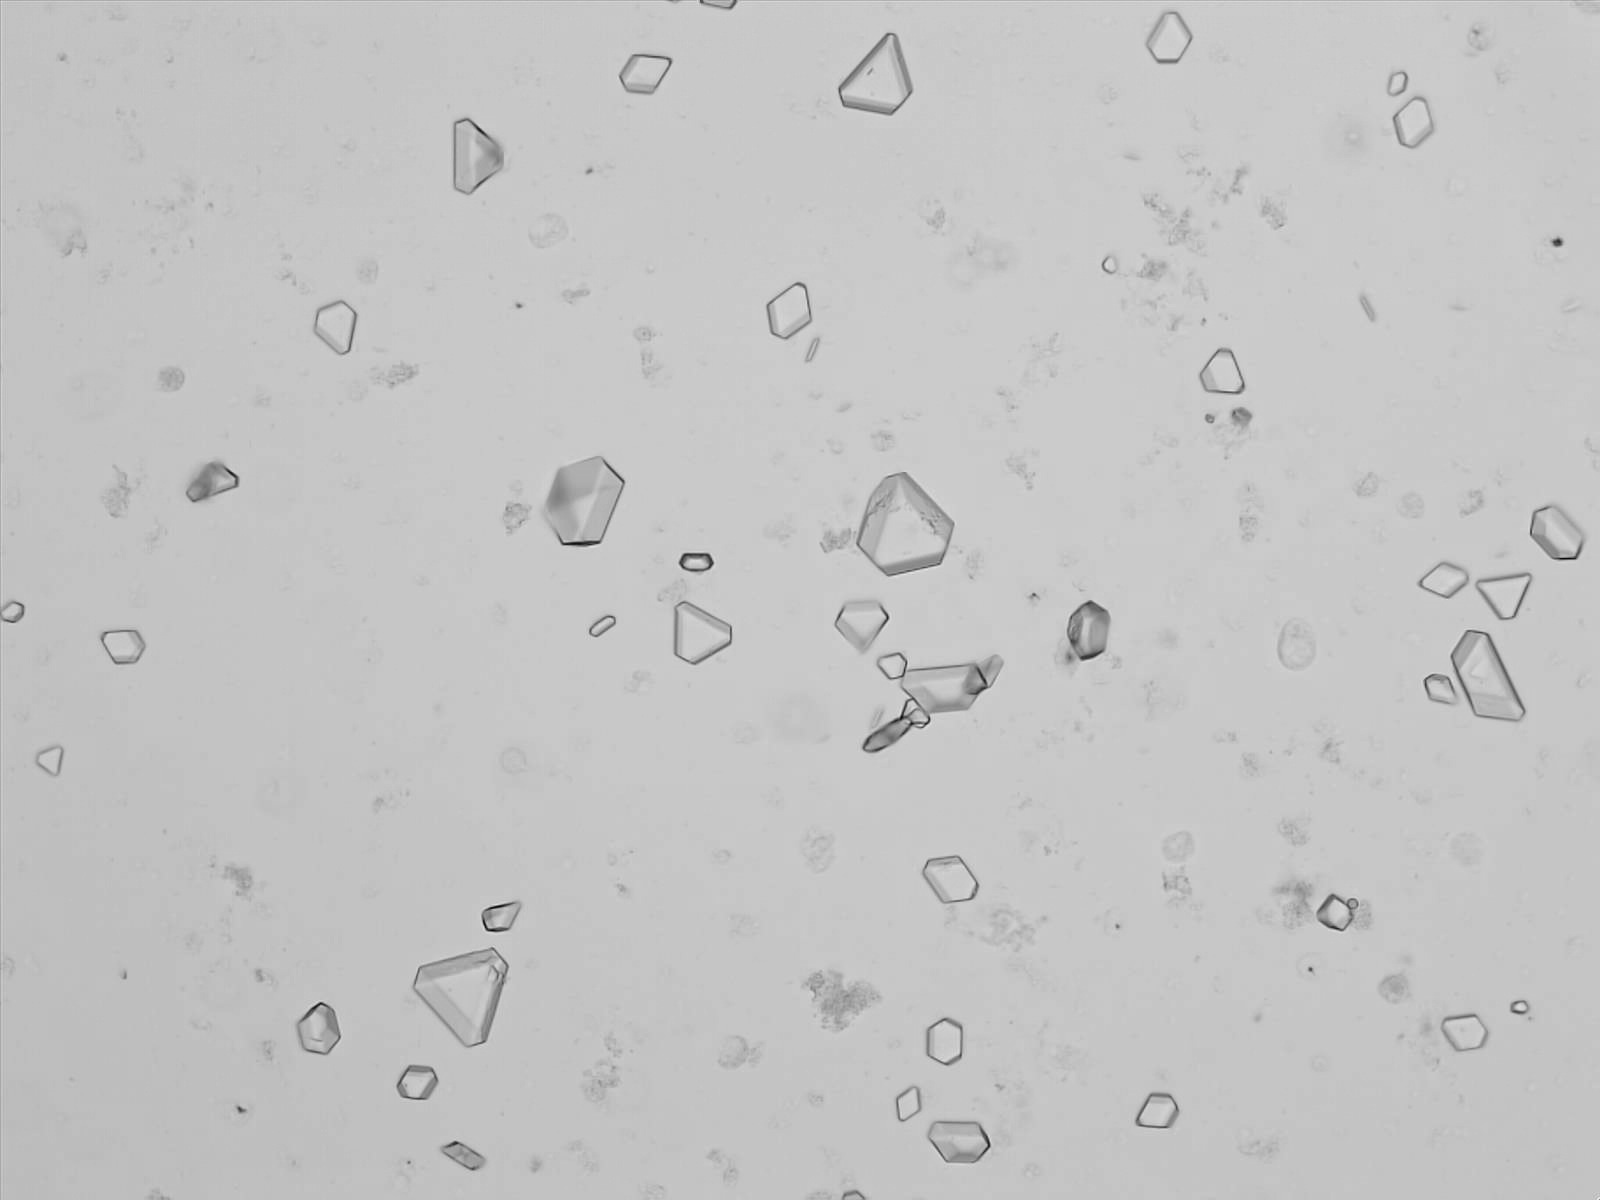

Triple phosphate - Triangle

Synonyms: Struvite, Magnesium ammonium phosphate, MgNH₄PO₄·6H₂O

Tripel phosphate, also known as struvite or magnesium ammonium phosphate (MgNH₄PO₄·6H₂O), are frequently found in alkaline urine and are typically associated with urinary tract infections caused by urease-producing bacteria such as Proteus, Klebsiella, Pseudomonas, Staphylococcus and Ureaplasma urealyticum. These bacteria convert urea in the urine to ammonia, which raises the pH of the urine to neutral or alkaline values. The higher pH promotes the precipitation of struvite.

This form of triple phosphate occurs mainly at very high pH (>9).